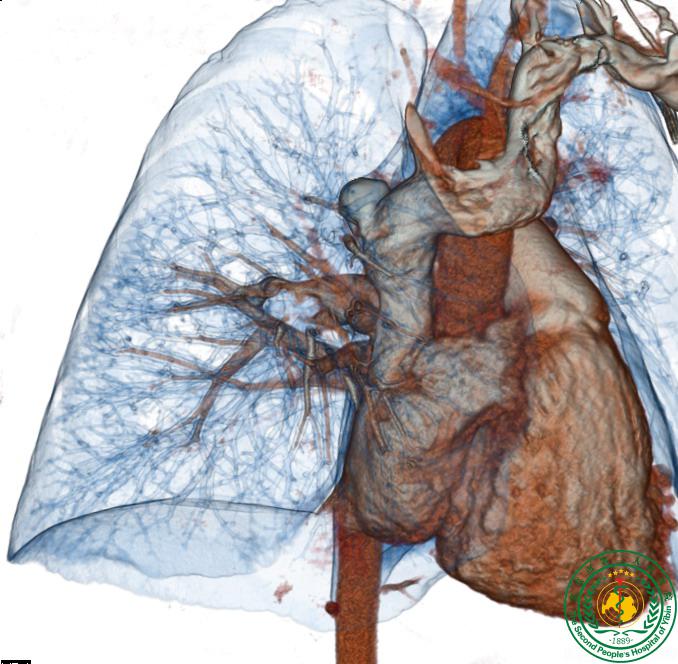

胸部重建                  左上肺肿瘤与肺血管